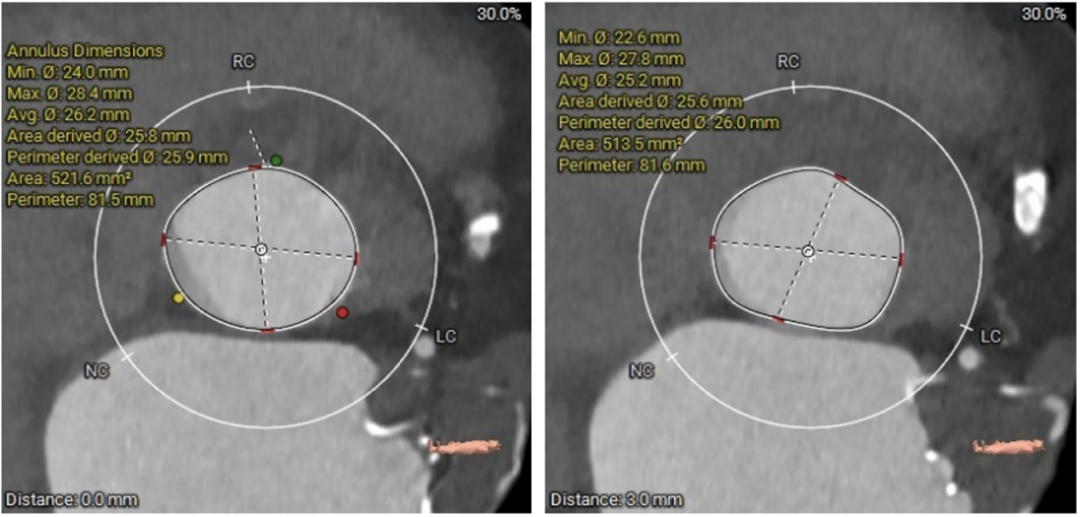

图1. 瓣环周长81.5mm,平均直径25.9mm。LVOT周长81.6mm,平均直径26.0mm